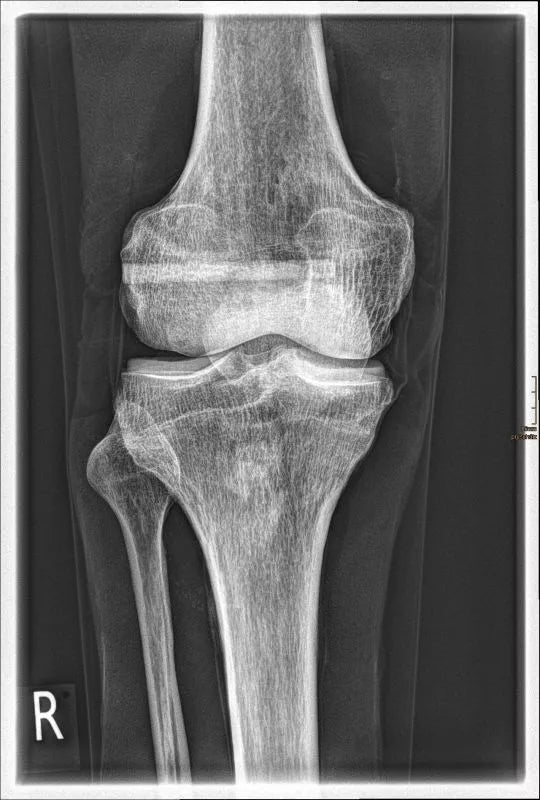

The whole-body X-ray phantom serves for practical training in projection radiography as well as in positioning and positioning techniques. It enables the production of realistic X-ray images under training conditions and depicts anatomical structures in their natural size.

The phantom contains a natural human skeleton. Additionally, the outlines of the larynx, lungs, heart, and kidneys are integrated, appearing as shadows on the X-ray images. This allows for the creation of images that accurately reflect the conditions found in patients. The use of a real skeleton enables the identification of bony landmarks that are not visible in plastic models.

The joints are mounted with full mobility, allowing positioning in common radiological standard positions, including special positions such as the frog position and pronation and supination of the forearm. The arms can be raised, so the phantom can also be used for bone examinations in CT scans. Particular attention was paid during assembly to the realistic representation of the joint spaces.

Each phantom is a handcrafted, unique piece. Variations in size, design, and appearance are possible. Depending on the model, pathological findings may be present. The revised design was developed in collaboration with a German training institution for medical-technical radiology assistants and meets the requirements of modern training concepts.